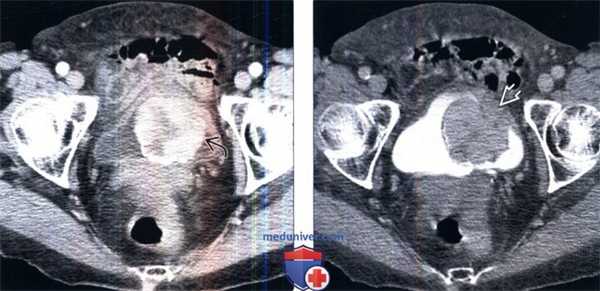

(Слева) КТ без контрастирования, аксиальный срез: у женщины 76 лет с макрогематурией и болью в малом тазу определяется крупное образование мочевого пузыря с частично кальцинированной поверхностью.

(Справа) КТ с контрастированием, аксиальный срез: у этого же пациента определяется прерывистое контрастирование объемною образования. Околопузырная жировая клетчатка, прилегающая к образованию, не имеет четких границ, что позволяет предположить пристеночное распространение этого процесса. (Слева) КТ с контрастированием, более каудальный аксиальный срез: у этого же пациента определяется прерывистое контрастирование объемного образования с зоной центрального некроза.

(Справа) КТ с контрастированием, аксиальный срез: у этого же пациента определяется прерывистое контрастирование объемною образования. Околопузырная жировая клетчатка, прилегающая к образованию, не имеет четких границ, что позволяет предположить пристеночное распространение этого процесса.